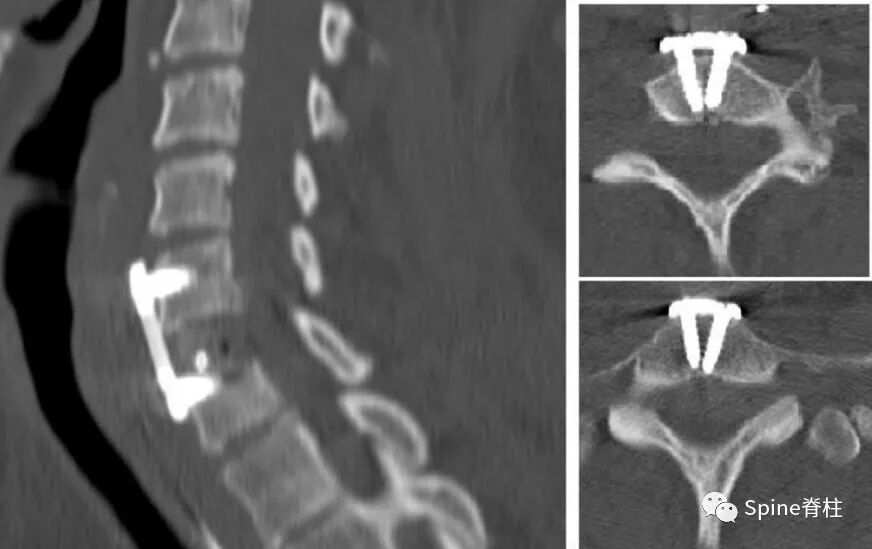

他们进行了一期颈后路钉棒固定(C3-T1)和二期左侧颈前入路,钢板取出,食道后壁破裂处,胸骨舌骨肌皮瓣修复。目前患者临床症状稳定,无椎前感染症状,经皮内镜胃造口术可获得营养。对于残余憩室,胸外科医师正在评估进一步的手术(憩室切除术或憩室固定术)。

图示:C6-7ACDF术后

图示:术后咽后感染并延伸至纵隔